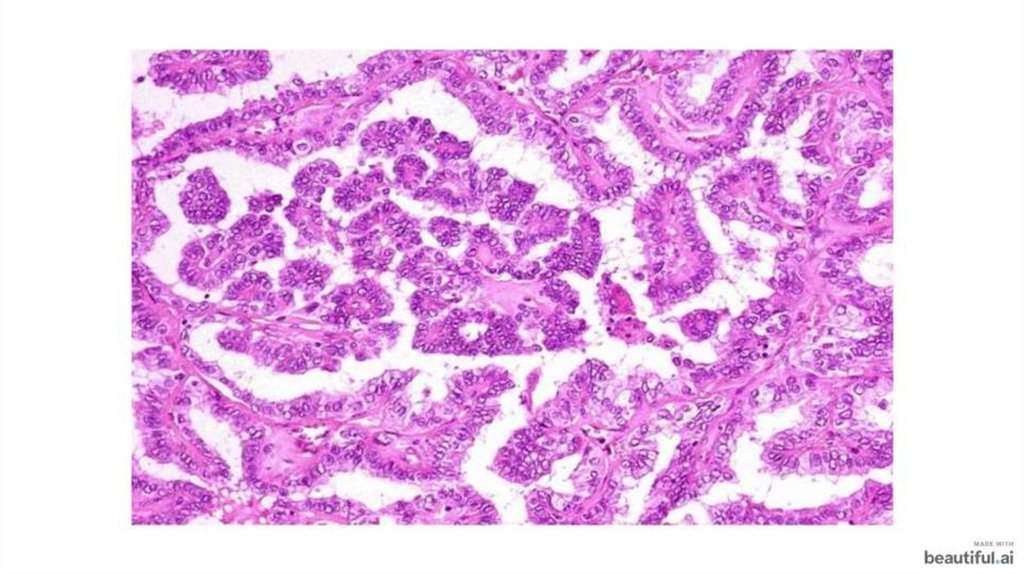

Фолликулярный и папиллярный рак щитовидной железы